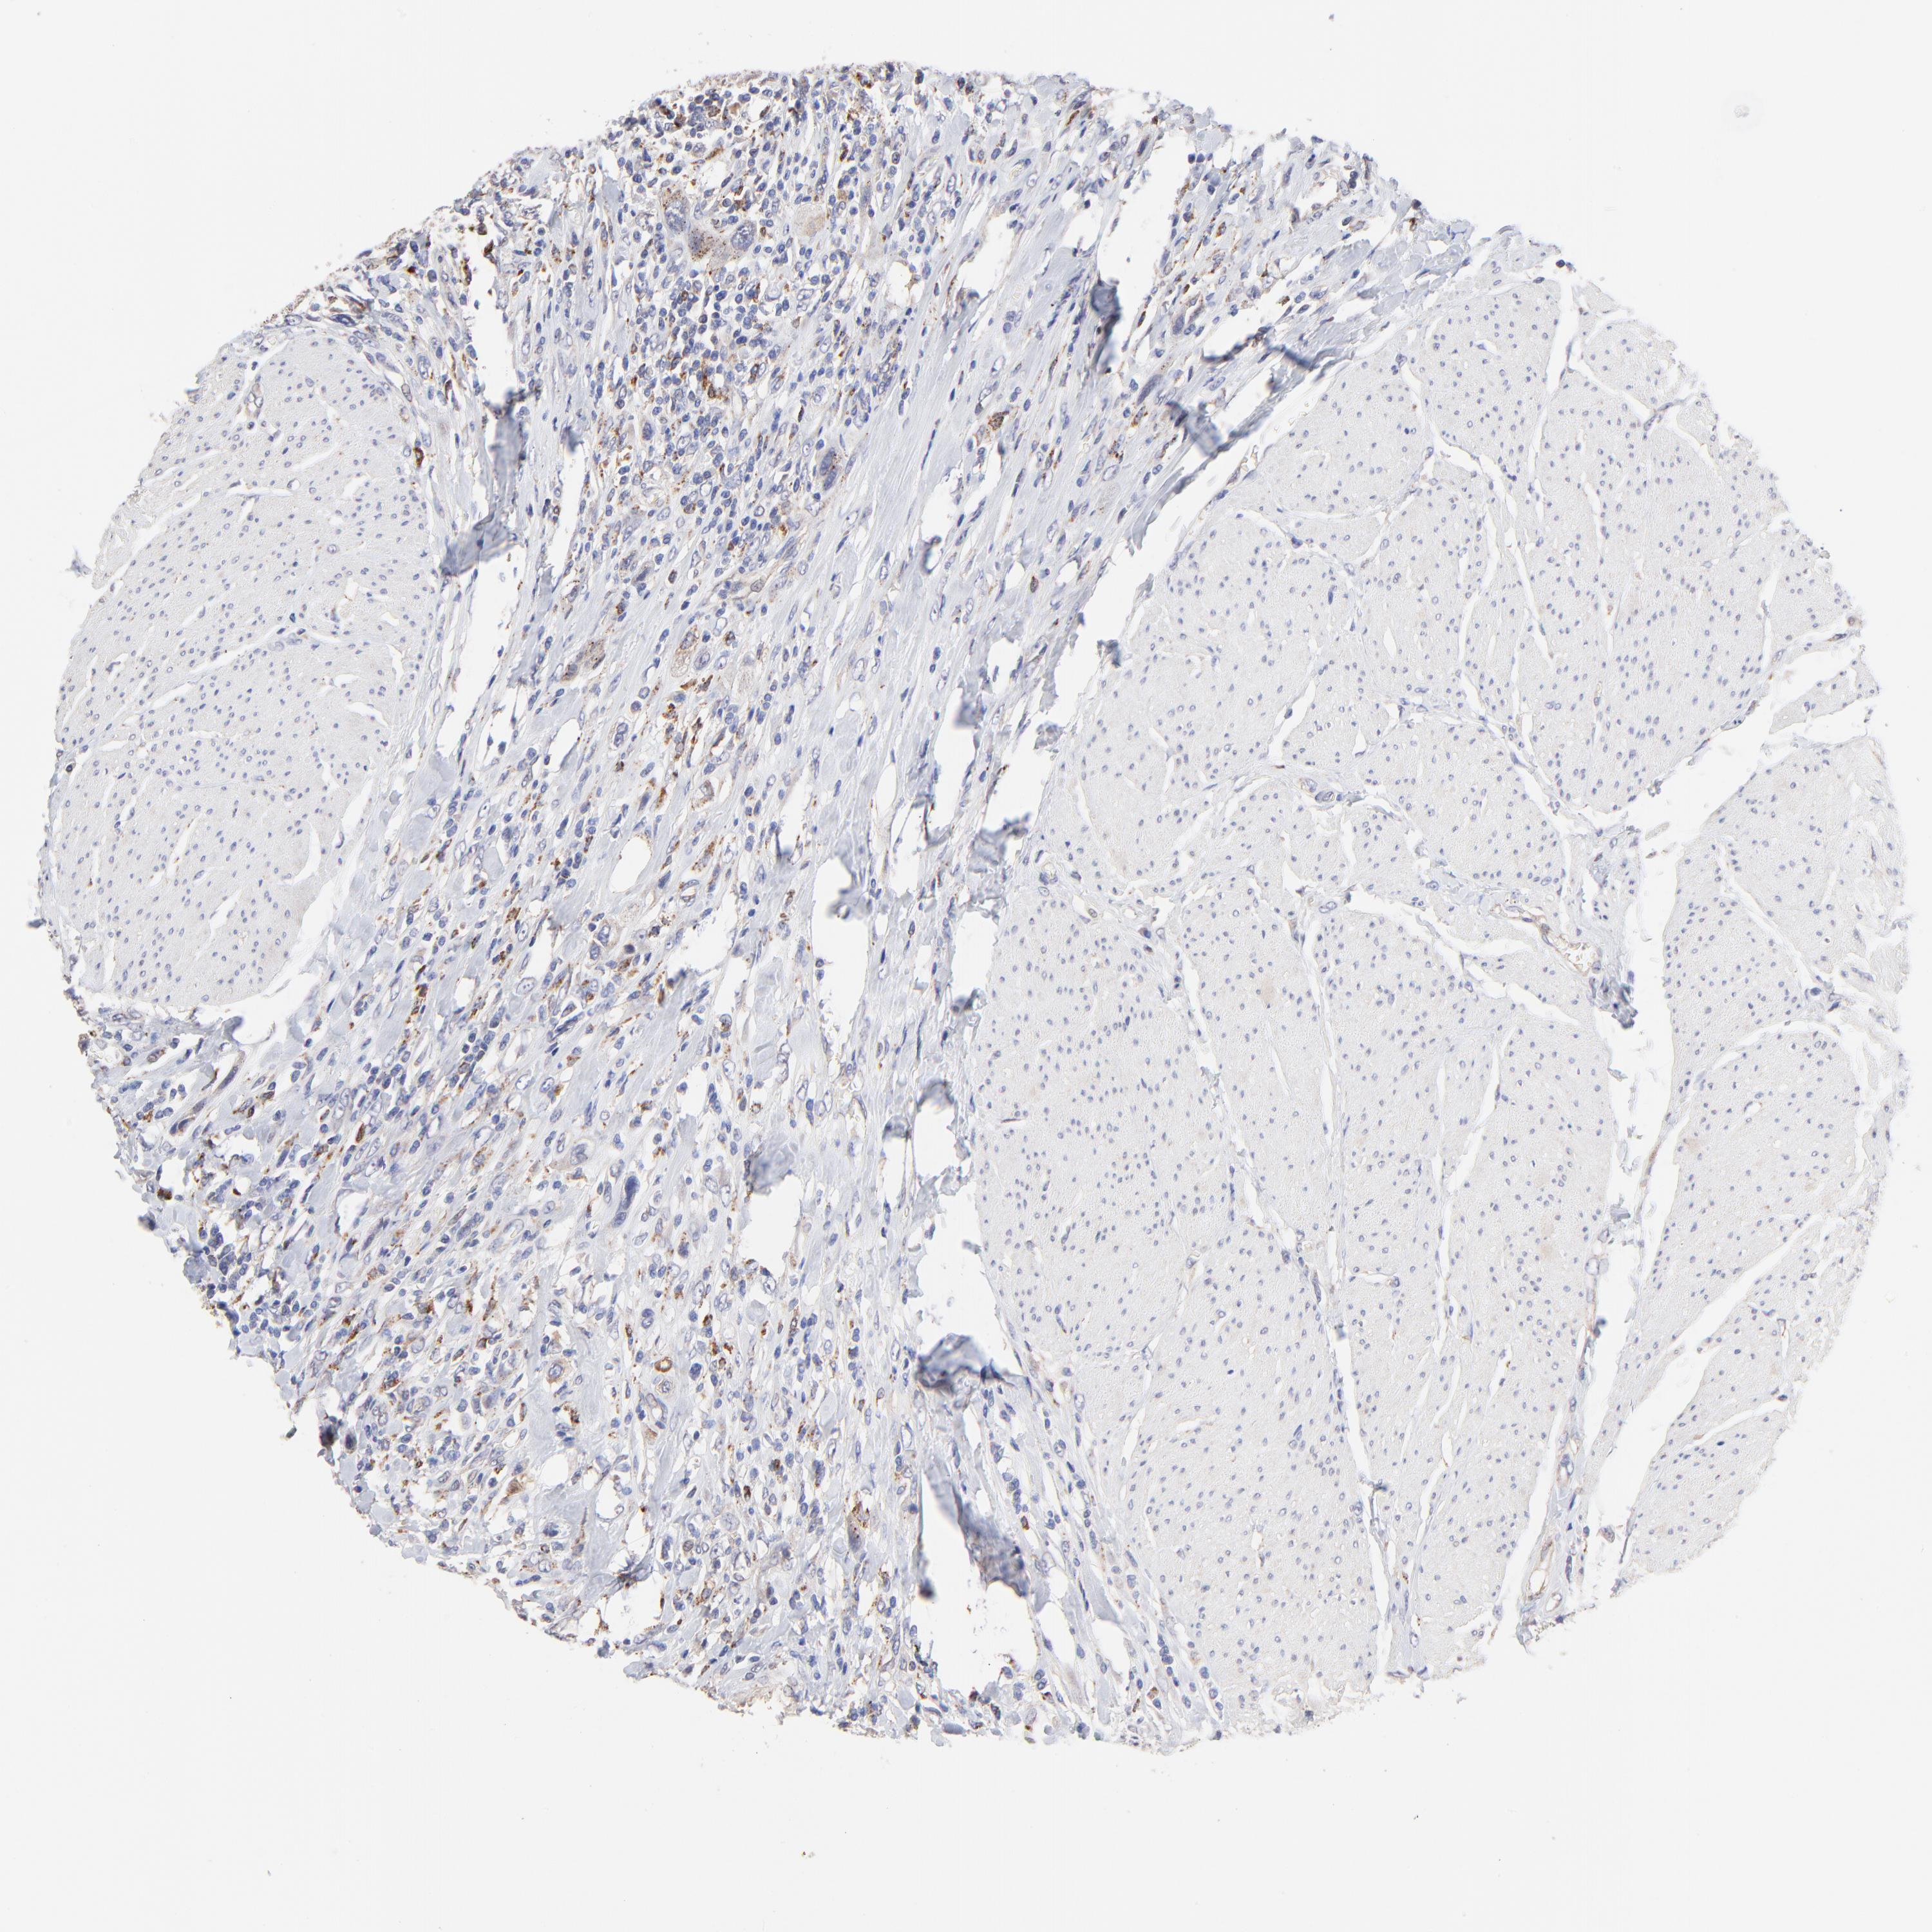

UROTHELIAL CANCER - Protein expressioni

A mouse-over function shows sample information and annotation data. Click on an image to view it in a full screen mode. Samples can be filtered based on level of antibody staining by selecting one or several of the following categories: high, medium, low and not detected. The assay and annotation is described here.

Note that samples used for immunohistochemistry by the Human Protein Atlas do not correspond to samples in the TCGA dataset.

Antibody stainingi

Antibody staining in the annotated cell types in the current human tissue is reported as not detected, low, medium, or high, based on conventional immunohistochemistry profiling in selected tissues. This score is based on the combination of the staining intensity and fraction of stained cells.

Each image is clickable and will lead to virtual microscopy that enables deeper exploration of all samples and also displays staining intensity scores, fraction scores and subcellular localization as well as patient and tissue information for each sample.

Antibody HPA003005

Staining

High

Medium

Low

Not detected

Intensity

Strong

Moderate

Weak

Negative

Quantity

>75%

75%-25%

<25%

None

Location

Nuclear

Cytoplasmic/membranous

Cytoplasmic/membranous,nuclear

Urothelial carcinoma, High grade

Urothelial carcinoma, Low grade